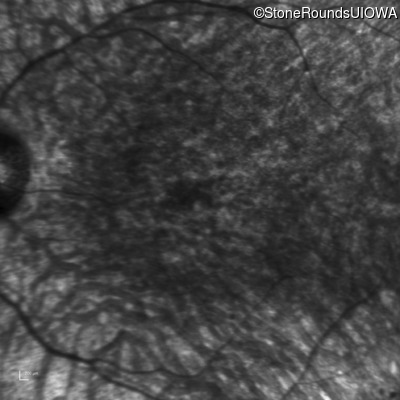

Infrared Fundus Photograph - Right - Hand Motion

Exemplar

Infrared Fundus Photograph - Left - Hand Motion